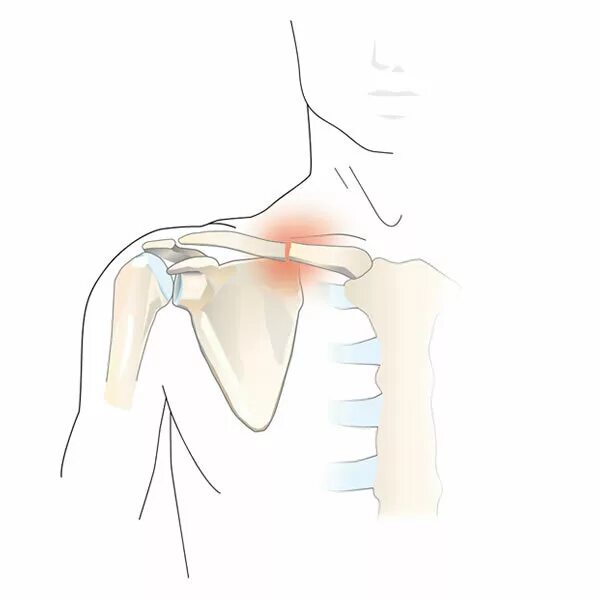

Хрустит ключица